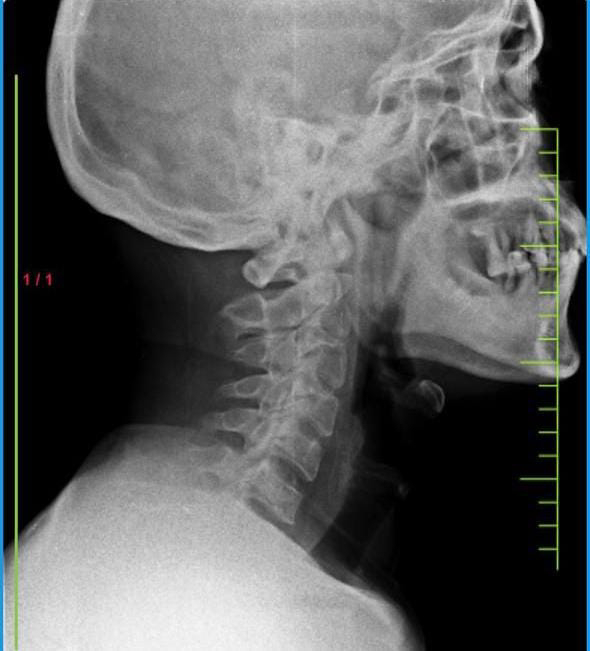

[12/26, 12:41 PM] PaJR PHR Moderator: 👆Picture of the anatomic and etiologic neurological localization in a simple cervical spine x-ray

[12/26, 12:43 PM] PaJR PHR Moderator: 👆Picture of the anatomic localisation where the same calcifications visible in the x-ray appear in black wavy shades behind the cervical vertebrae along the posterior longitudinal ligament